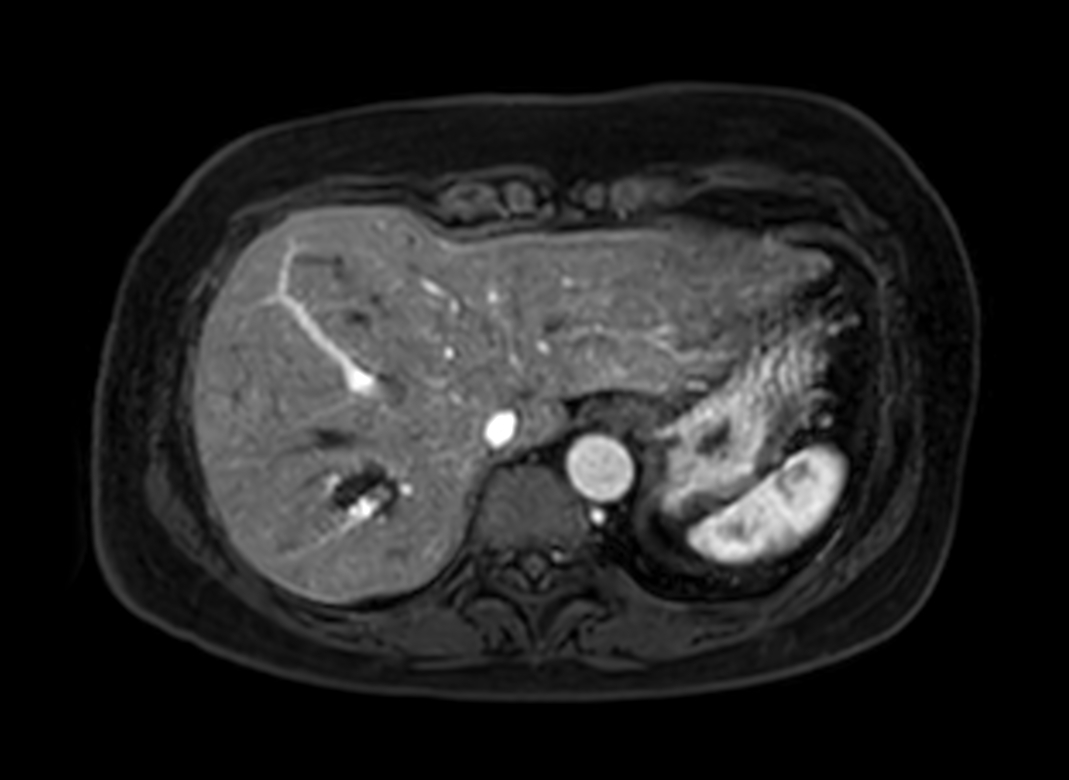

Axial eTHRIVE (1st dynamic)

Axial eTHRIVE (2nd dynamic)

Axial eTHRIVE (4th dynamic)

Axial eTHRIVE